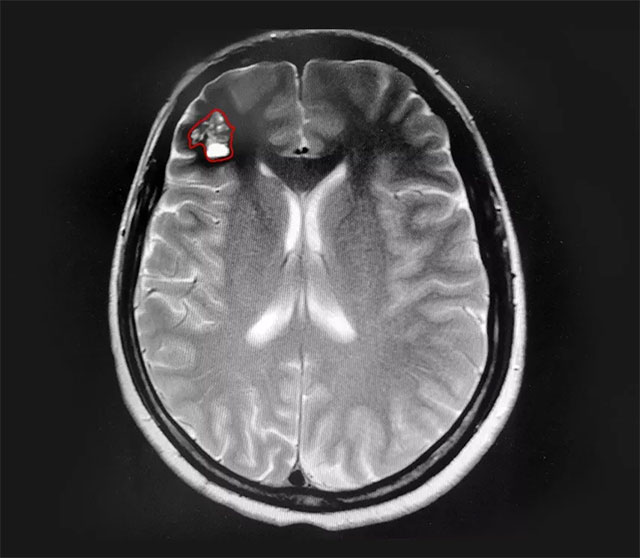

▲ 患者右侧额叶可见桑葚样团块

患者的头晕症状持续数年且于近期加重,已影响正常生活,结合病情进展和影像学资料,沈建康教授和神经外科6A病区侯增欣主任等专家开展了严谨的评估和讨论,认为患者具有手术指征。在告知手术风险并取得家属同意后,由沈建康教授主刀,为钱女士行血管瘤切除手术。

在电生理监测的保驾护航下,沈教授利用神经导航技术成功定位病变部位,并采用经脑沟入路技术,减少患者脑部皮质损伤直达病变部位。显微镜下可见,病变部位呈褐色桑葚状,周围脑组织黄染。“这是由于海绵状血管瘤自发性反复小量出血,造成的铁血黄素沉着。”沈教授解释道。借助先进的神经导航技术,在蔡司显微镜(双荧光)下,沈教授顺利切除血管瘤,并剔除黄染组织,术中无明显副损伤。